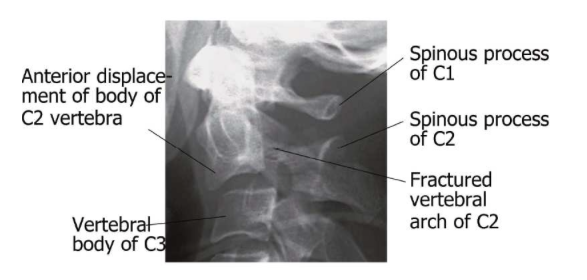

What is hangman’s fracture?

Fracture of C2

*Typically the dens